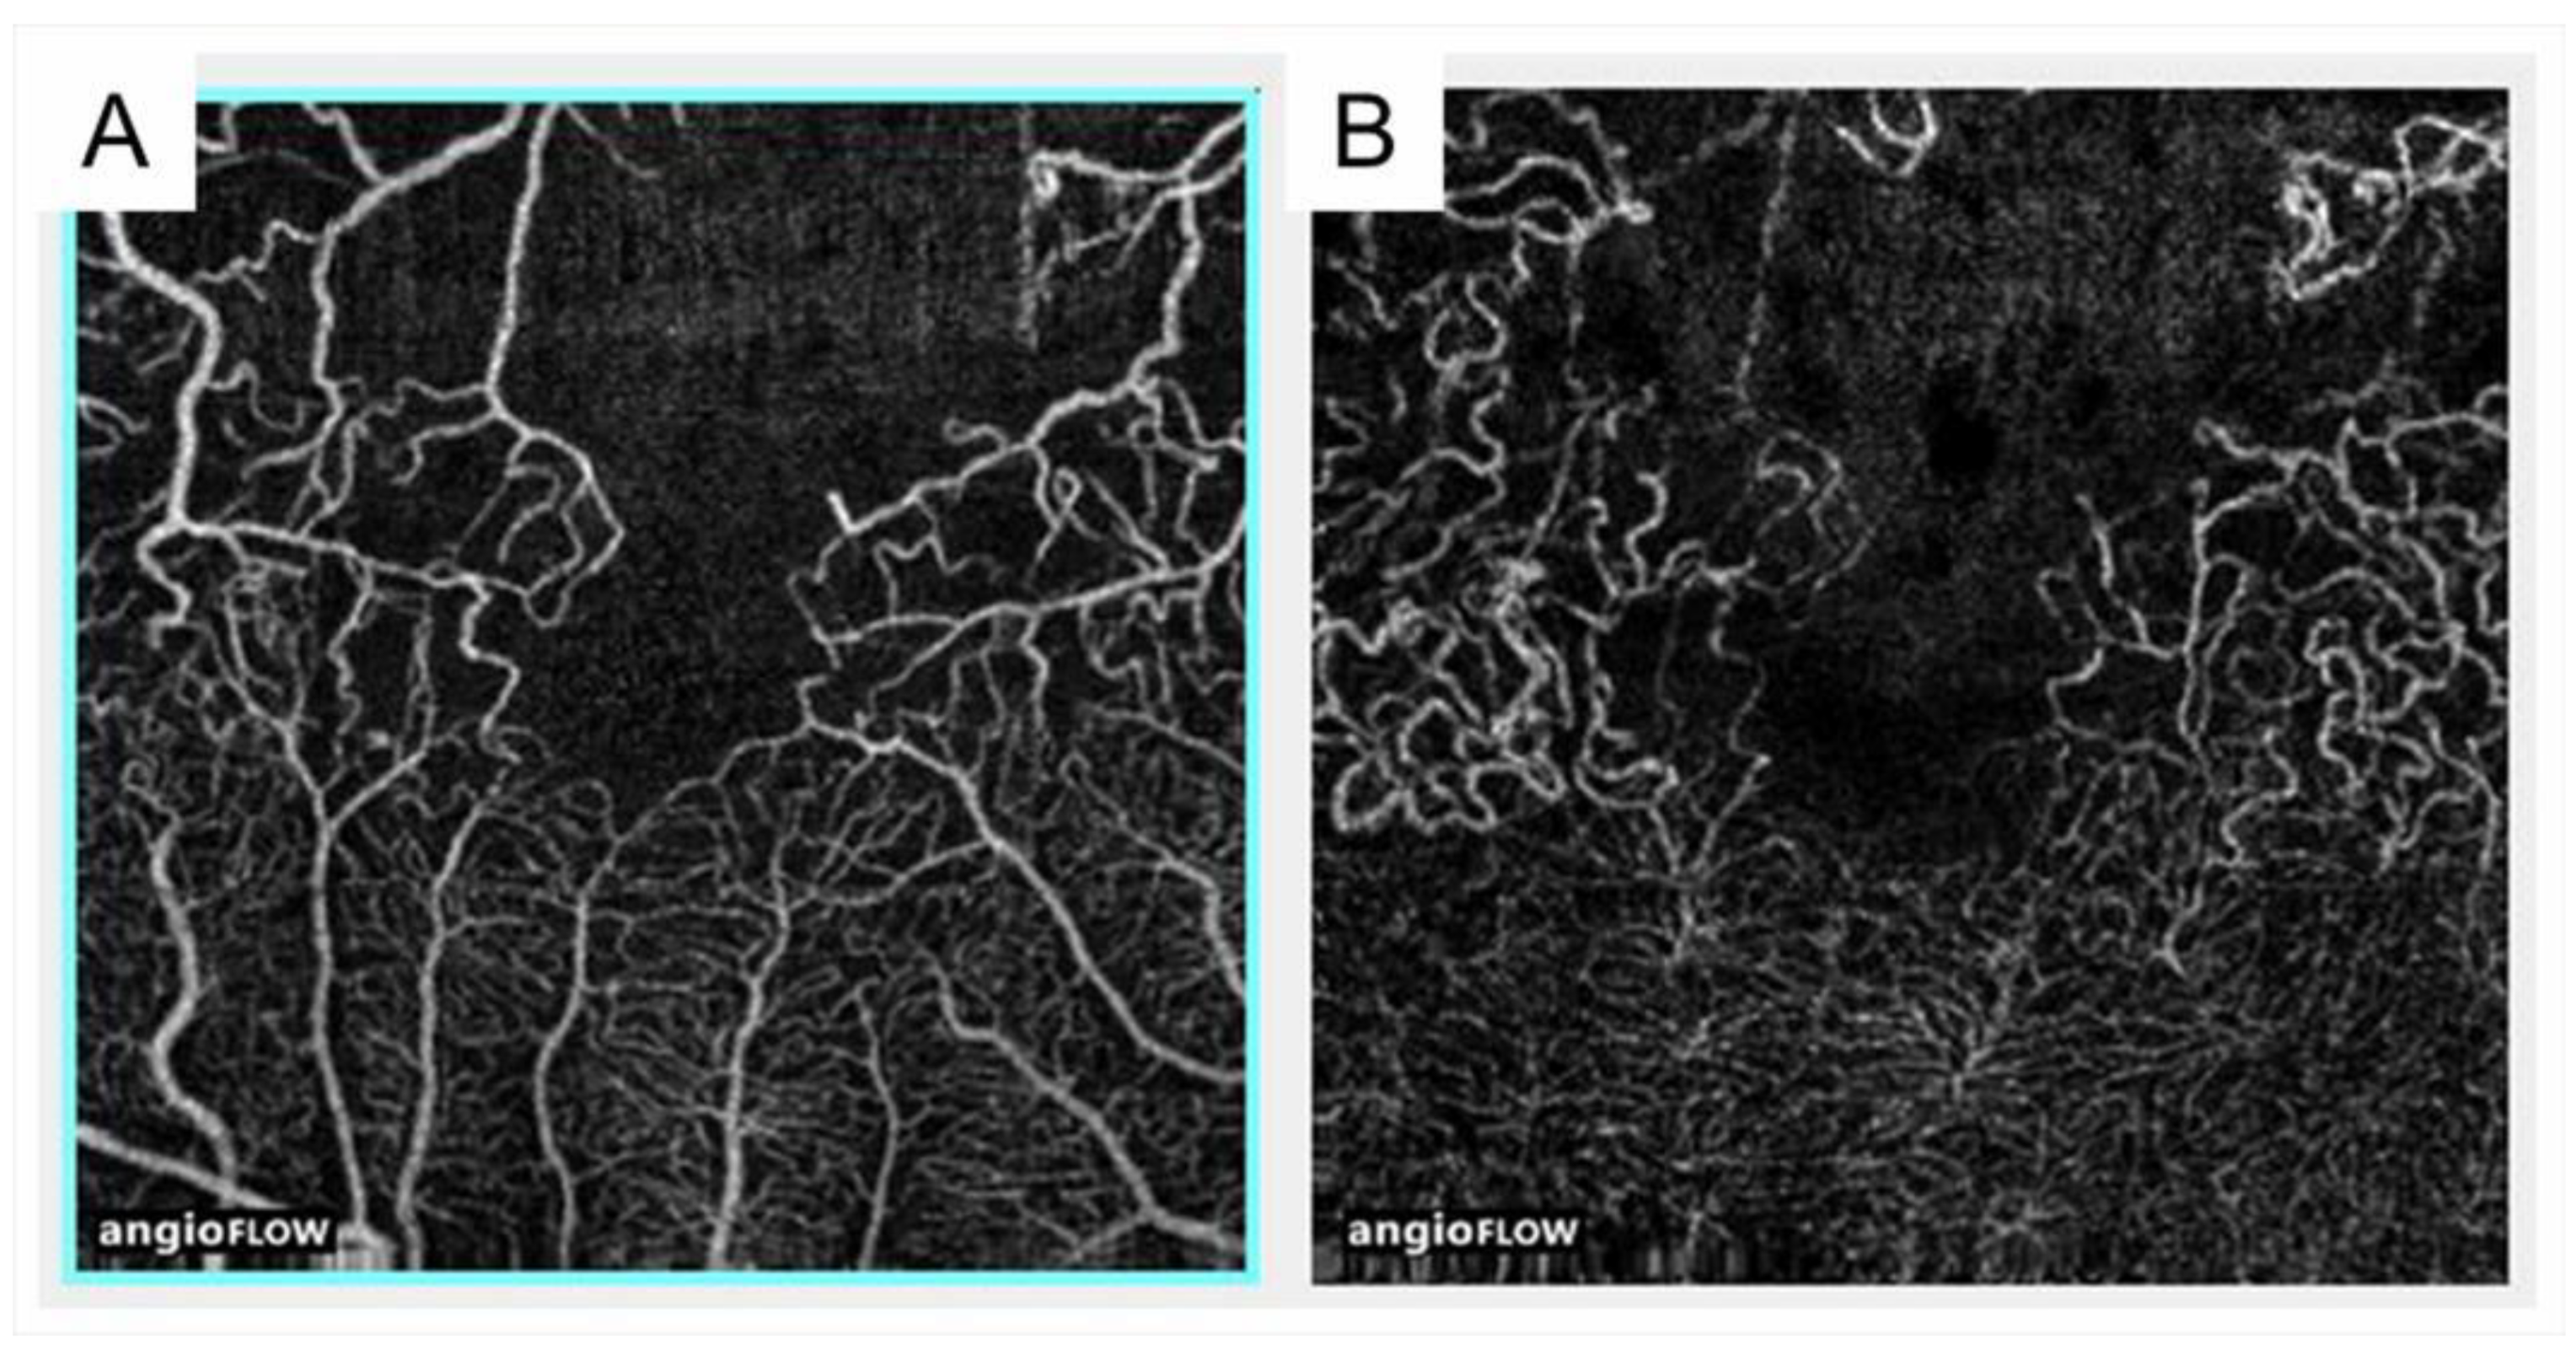

3.8. Microaneurysm and Macroaneurysm

- Suzuki, N.; Hirano, Y.; Yoshida, M.; Tomiyasu, T.; Uemura, A.; Yasukawa, T.; Ogura, Y. Microvascular abnormalities on optical coherence tomography angiography in macular edema associated with branch retinal vein occlusion. Am. J. Ophthalmol. 2016, 161, 126–132.e1. [Google Scholar] [CrossRef] [PubMed]

- Esaki, Y.; Hirano, Y.; Kurobe, R.; Yasuda, Y.; Tomiyasu, T.; Suzuki, N.; Yasukawa, T.; Yoshida, M.; Ogura, Y. Morphologic classifications and locations of microaneurysms and clinical relevance in branch retinal vein occlusion. Clin. Ophthalmol. 2020, 14, 1909–1919. [Google Scholar] [CrossRef]